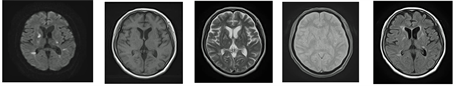

Figure 1. (a) Magnetic resonance imaging (MRI) findings of patient 1 showed a high intensity area in putamen and caudate nucleus in T1-weighted image (T1-WI); (b) Multiple small hyperintensities in both periventricular sides in diffusion weighted image (DWI) and fluid-attenuated inversion recovery (FLAIR), with normal looking putamen and caudate nucleus in T1-WI of patient 2. DWI; diffusion weighted image, T1-WI; T1-weighted image, T2-WI; T2-weighted image, T2*-WI; T2*-weighted image, FLAIR; fluid-attenuated inversion recovery.

data showed plasma glucose at 1290 mg/dL and pH at 7.34, but no ketonuria. After hospitalization, she started presenting right side hemiballism. We started her on an insulin and saline intravenous infusion. After 6 days, we performed a head MRI and found multiple small hyperintensities in both periventricular sides by DWI and fluid-attenuated inversion recovery (FLAIR) (Figure 1(b)). T1-WI showed no lesions in putamen and caudate nucleus. There was no evidence of carotid plaques, atherosclerosis of brain arteries, or arrhythmia. We diagnosed her as having DC with hyperosmolar hyperglycemic state. We controlled hyper glycemia using insulin injections. We administered haloperidol at 0.75 mg/day and gradually increased up to 2.25 mg/day. After glycemic control and haloperidol administration, the choreic movement improved and the patient was able to self-administer insulin injection (final dose of insulin; insulin glargine U300 19 U, insulin glulisine 2-2-2 U). She was transferred to another hospital for further rehabilitation on twenty-ninth hospital day.

Patient 1 showed the typical MRI findings of DC. Because SU and DPP-4I combinations are known to cause hypoglycemia [7] , and the patient presented no hyperglycemia on admission, we considered that the use of SU and DPP-4I may have led to hypoglycemia and subsequent DC. There is also been a report of an elderly woman with type 2 diabetes and hypoglycemia associated with insulin treatment that led to DC [6] . It is possible that the hypoglycemia also associated with diabetes therapy in elderly patients may cause DC. A case series of 53 patients with DC revealed that all patients showed a high intensity in basal ganglia on the MRI T1-WI [4] . Hyper intensity in basal ganglia is a typical MRI finding and supports the clinical diagnosis of chorea in patients with diabetes. On the other hand, some cases showed no abnormalities in the basal ganglia using brain MRI [5] [8] . One case showed leukoaraiosis and multiple cortical ischemia, but no hyperintensisty in putamen [9] . A recent study reported that a DC patient with nonketoic hyperglycemia did not show any abnormalities in the brain MRI and computed tomography (CT) [10] . In our case, patient 2 did not show typical DC symptoms, such as high intensity area in basal ganglia in the brain MRI. Instead, we found multiple small hyperintensities in both periventricular sides in the DWI, but the typical putamen high intensity on the T1-WI was not found. Hyperviscosity caused by extreme hyperglycemia may produce a transient microcirculatory dysfunction of the striatum [11] . Recently, some patients had been reported to present chorea due to essential thrombocythemia or polycythemia vera [12] [13] . We think it is possible that hyperviscosity due to extreme hyperglycemia led to multiple cerebral thromboembolisms in our patient 2. In addition, the lack of evidence for atherosclerotic lesions in the carotid artery ultrasonography and the brain magnetic resonance angiography added to a lack of arrhythmias support the notion that these multiple small hyperintensities did not represent atherosclerotic lesions in our patient 2. Chang et al. proposed two types of DC: a common type showing hyperglycemia, choreic movement with typical radiographic imaging in brain MRI or CT and uncommon type showing chorea with negative imaging changes [10] . Patient 2 exhibited uncommon type of DC. However, there is no clear evidence about the uncommon DC. It is, therefore, necessary to report such patients.